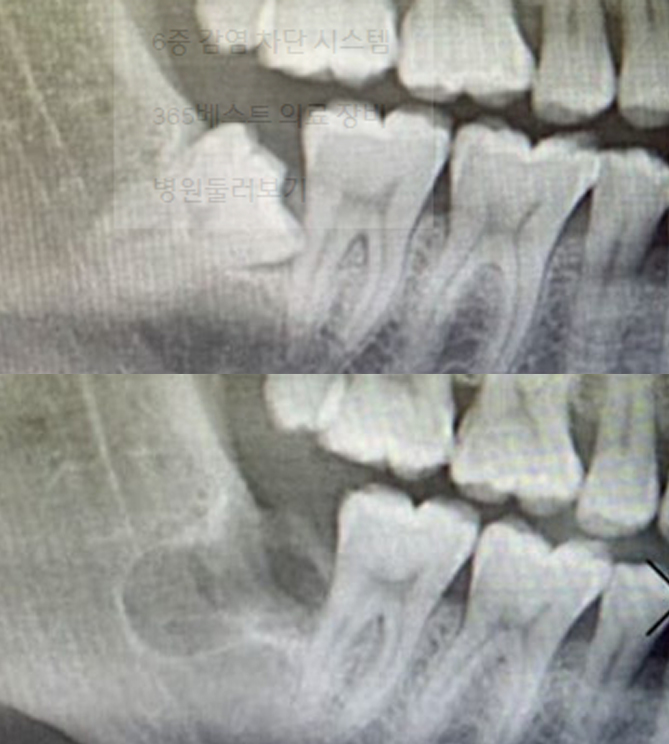

전후사진